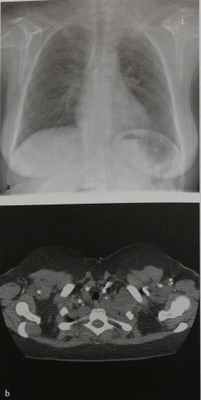

Неврилеммома у мужчины 48 лет. На обзорной рентгенограмме грудной клетки видно округлое образование с гладкими контурами, расположенное паравертебрально в нижнем отделе заднего средостения. Даже в отсутствие расширения межпозвонкового отверстия локализация объемного образования дает основание думать, что оно, скорее всего, имеет нейрогенное происхождение. Диагноз неврилеммомы подтвердился на операции.

Нейрофиброма у женщины 38 лет.

На обзорной рентгенограмме грудной клетки верхний отдел средостения расширен в обе стороны, но больше слева в области верхней апертуры грудной клетки. Еще одна опухоль, имеющая мягкотканную плотность, расположена латеральнее вдоль ребер в левом верхнем легочном поле. Имеется также локальное затемнение в области корня правого легкого.